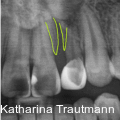

Die interdisziplinäre Zusammenarbeit spielt in der modernen Kieferorthopädie eine zentrale Rolle, insbesondere bei komplexeren Behandlungsfällen, die über das alltägliche Behandlungsspektrum hinausreichen. Fotos: © Dr. Johanna Katharina Trautmann